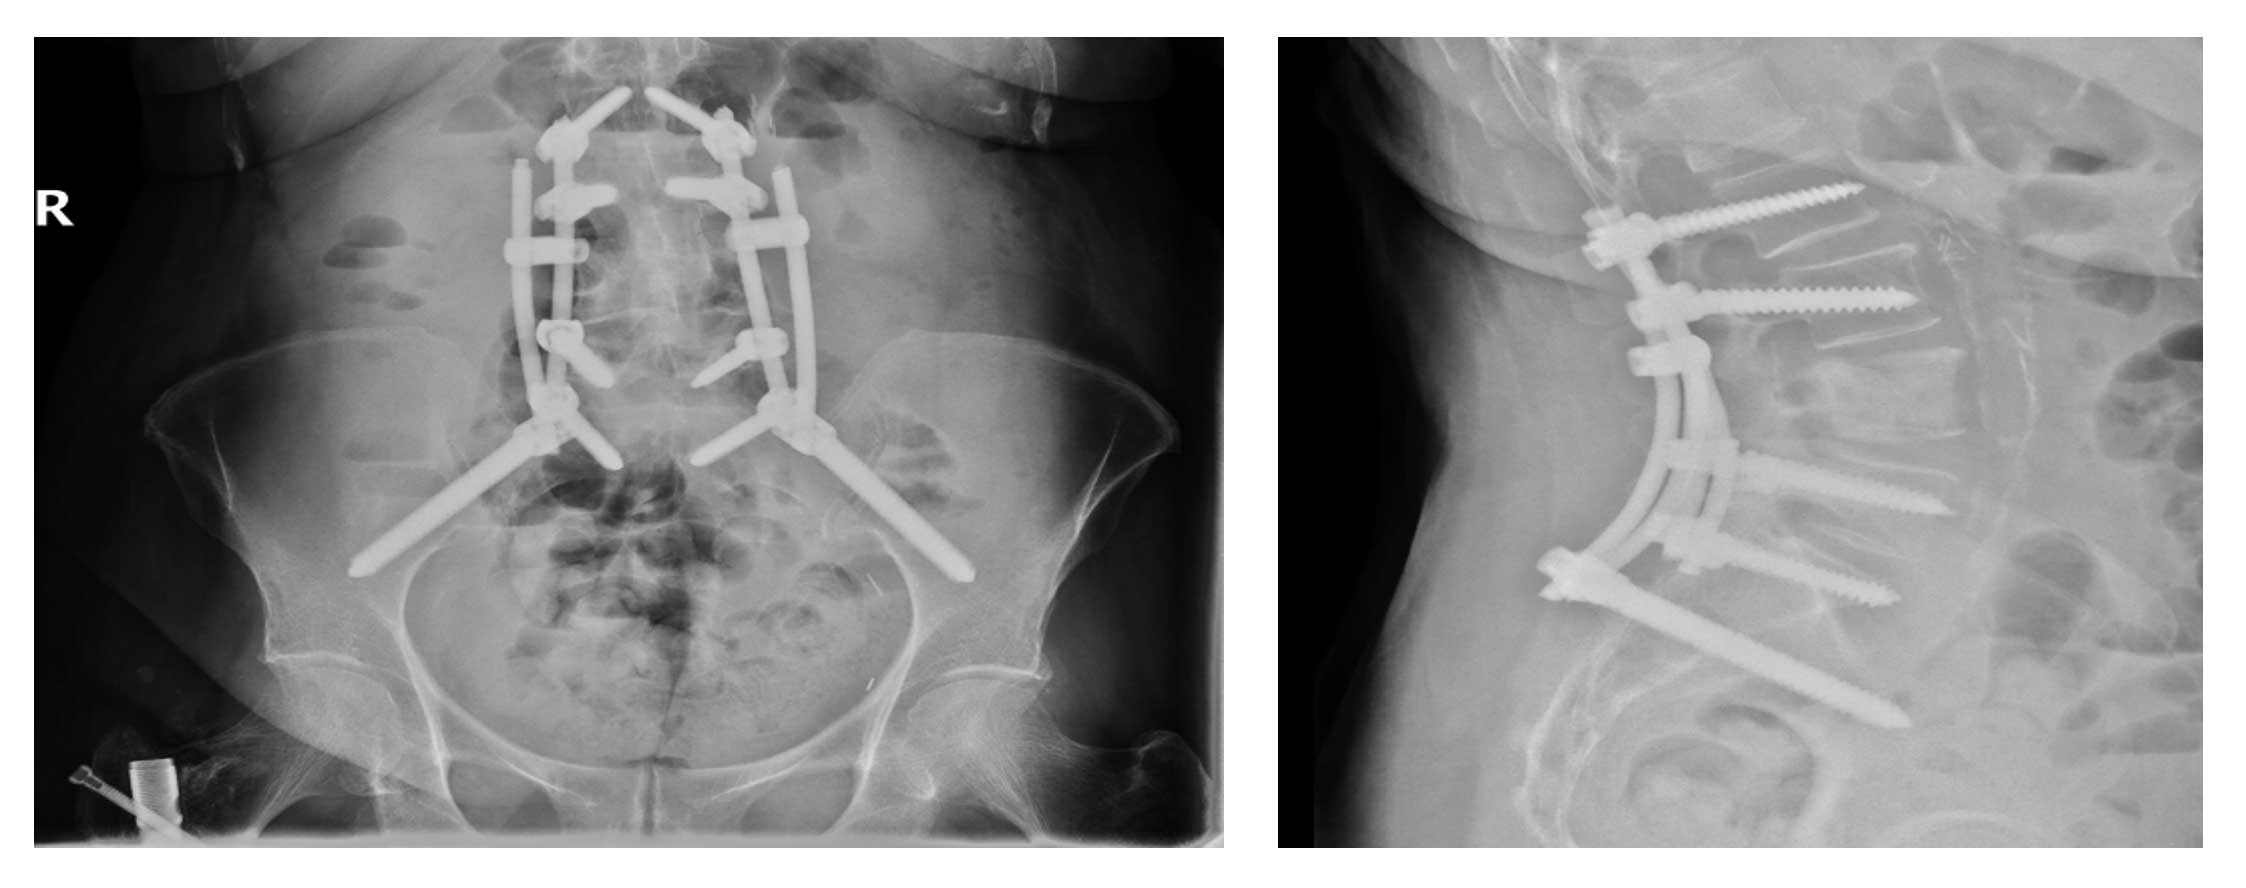

Ameliyat sonrası: Röntgende L4 omurgaya uygulanan çimentolama ve yeniden vidalama işlemi ile güçlendirme görülmekte.